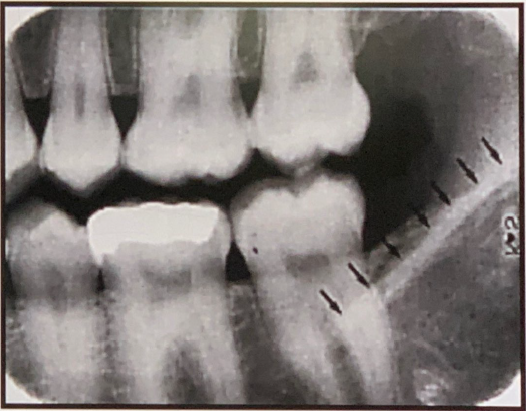

83. what does arrow show?

Hamular notch

• Shape: Narrow, curved radiolucent depression. • Location: Just behind the last maxillary molar (maxillary tuberosity), extending toward the pterygoid plates. • Medially: Ends at or near the hamulus, which appears as a small, pointed radiopaque structure.